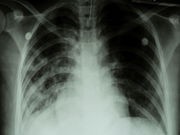

Tuberculosis (TB) is a bacterial infection affecting the lungs and sometimes other organs. Overall, TB cases in the United States decreased over the past two decades, but TB cases among foreign-born people remained higher than in the general population, the study authors said.